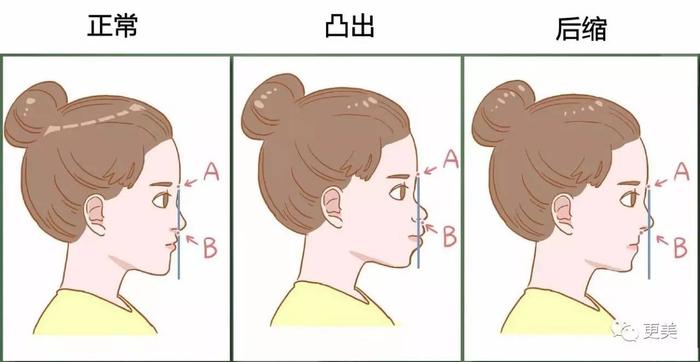

——搞清楚是哪种嘴凸——

而嘴凸也分牙性和骨性的,要确定自己属于哪种情况必须要去拍片哦

通常会拍到这三种情况,额头到牙齿画线,上颌没有超线的,就是牙性问题;如果超出了,可能就是骨性问题了